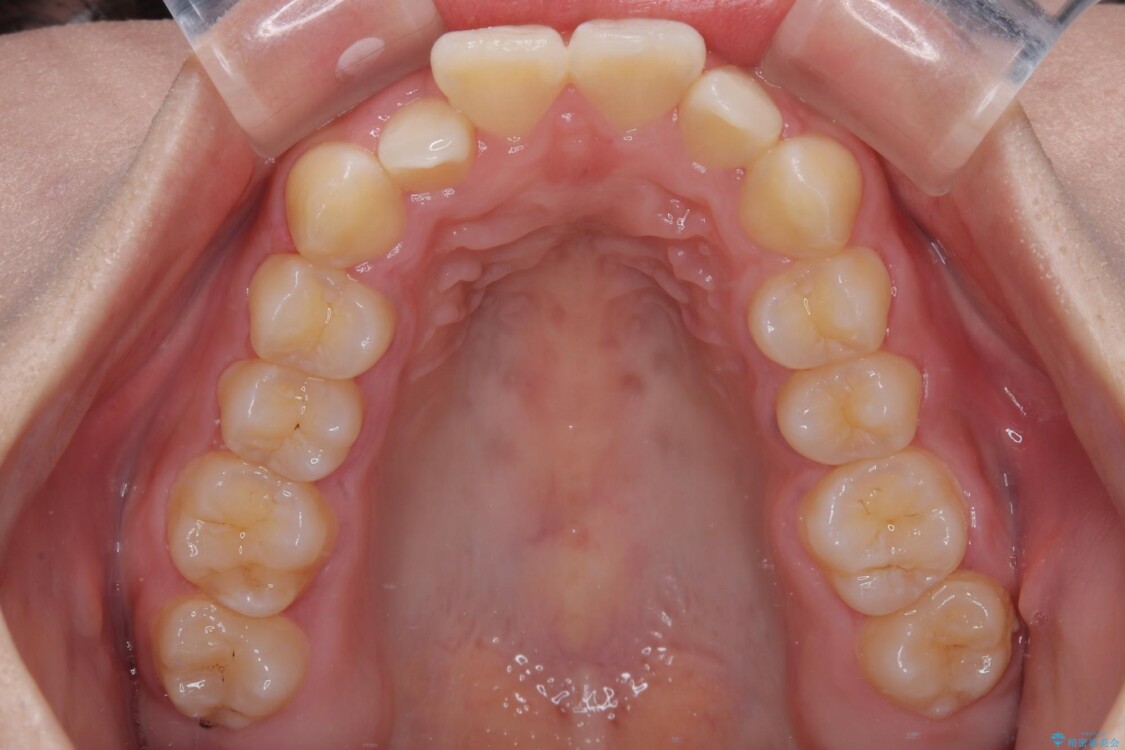

歯列アーチが狭くスペース不足により前歯がデコボコしている状態でした。見た目を改善しつつ、前歯を前方に突出させず、自然な笑顔を目指したいというご希望でした。

・アーチを側方に拡大して歯が並ぶスペースを確保

治療前

• 目立ちにくい表側装置で1年完了!狭いアーチを側方拡大し前歯のデコボコを整えた症例 治療前画像